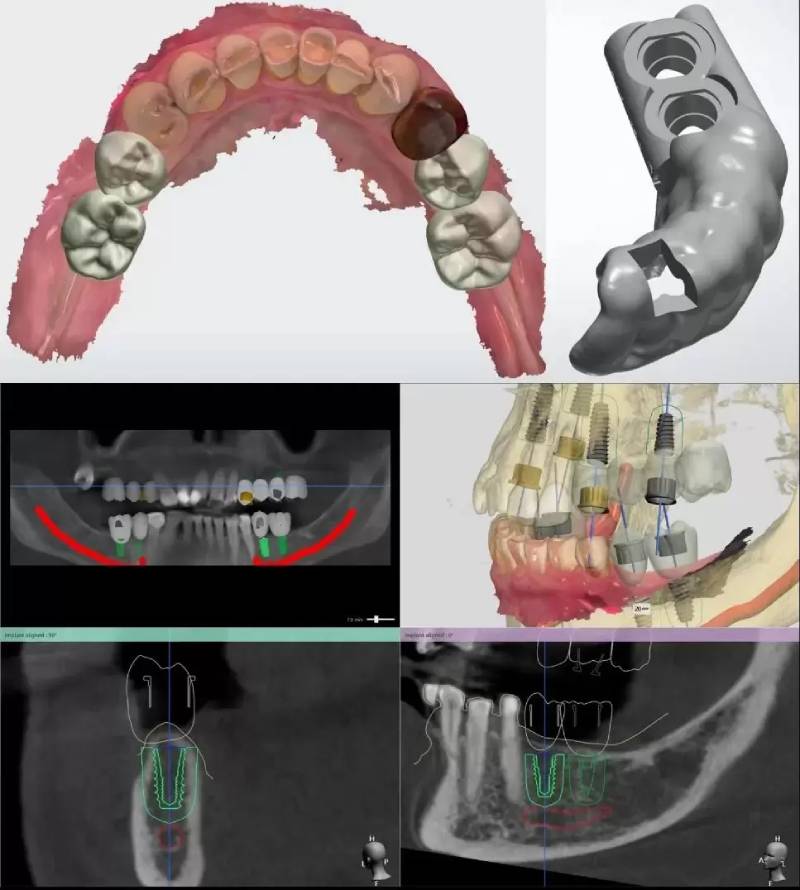

Quy trình trồng răng cửa theo phương pháp trồng răng Implant cá nhân hóa DCT gồm các kỹ thuật được tối ưu thời gian và độ chính xác dựa vào máy móc, thiết bị hiện đại như sau:

• Bước 1: Lấy dữ liệu về tình trạng xương hàm bằng máy CT Cone Beam và đưa vào phần mềm giả lập để lập kế hoạch đặt trụ đúng hướng, đúng vị trí, đồng thời sản xuất máng hướng dẫn phẫu thuật Guidelinetrụ lành thương cá nhân hóa.

• Bước 2: Đặt trụ Implant vào xương hàm nhờ vào máng hướng dẫn phẫu thuật Guideline, thời gian đặt trụ được rút ngắn chỉ từ 7 - 10 phút/trụ.

• Bước 3: Sau khi đặt trụ Implant, trụ lành thương sẽ được đặt nhằm hỗ trợ quá trình lành thương, tái lập hình thể giải phẫu lợi giúp khôi phục chức năng thẩm mỹ cho khuôn miệng.

• Bước 4: Sau khi trụ Implant đã tích hợp ổn định, cô chú/anh chị sẽ được lấy dấu mẫu hàm bằng máy quét Scanning để lấy dấu khuôn hàm, dấu răng nhằm thiết kế trụ phục hình cá nhân hóa và mão răng sứ phù hợp.

• Bước 5: Dữ liệu đã được Scanning sẽ được đưa vào phần mềm Exocad để thiết kế trụ phục hình cá nhân hóa và mão răng sứ dựa vào khuôn mặt và đặc điểm mô nha chu của cô chú/anh chị.

• Bước 6: Sau quá trình thiết kế, dữ liệu được chuyển qua bộ phận CAM (bộ phận chế tác) để sản xuất trụ phục hình cá nhân hóa và mão răng sứ. Trụ phục hình sẽ được sản xuất từ Zirconia hoặc Titanium thuần chất, mão răng sứ sẽ được đúc nguyên khối từ Zirconia đa lớp.

• Giải pháp trồng răng Implant cá nhân hóa DCT áp dụng các máy móc hiện đại tiên tiến vào quá trình phẫu thuật

Giải pháp trồng răng Implant cá nhân hóa DCT áp dụng các máy móc hiện đại tiên tiến vào quá trình phẫu thuật